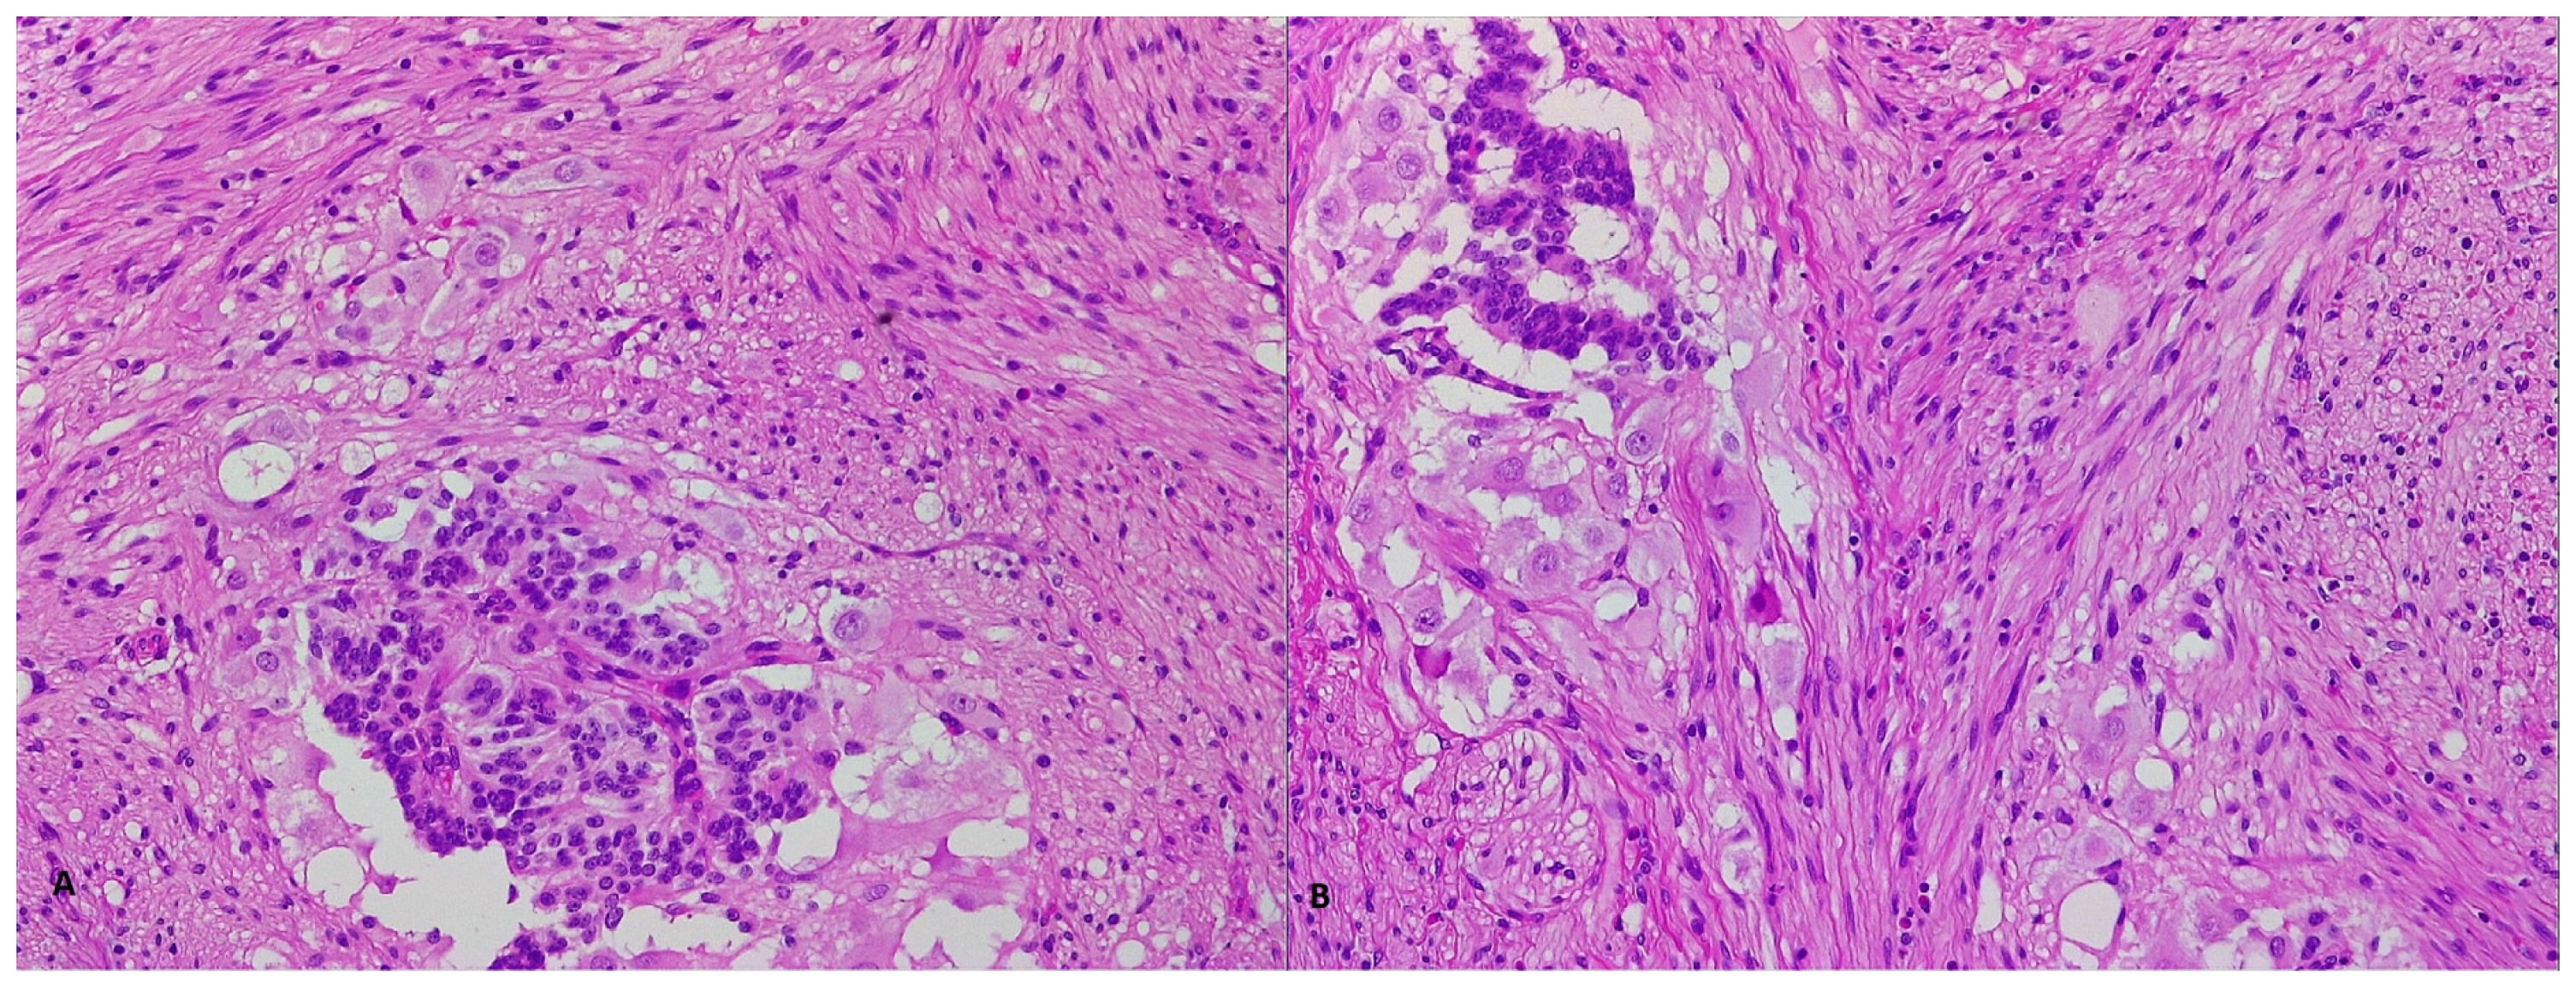

2. Case Report 1

3. Case Report 2

4. Case Report 3